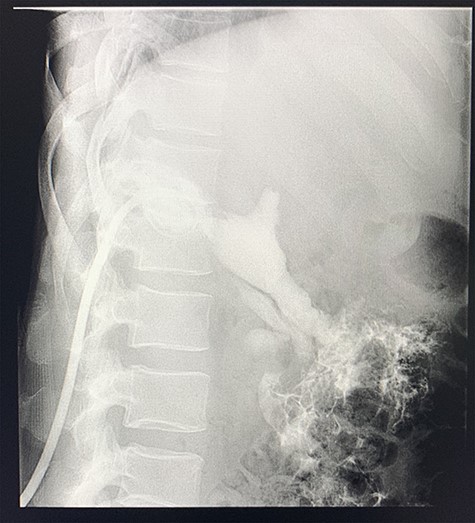

A computed tomography (CT) scan of the abdomen revealed an enlarged, thickened gallbladder with multiple stones, communicating with an intrahepatic collection in segment 4 measuring 116 × 80 mm, with an associated air fluid level and air locules (Fig. 1). There was an apparent fistulous tract to the hepatic flexure of the colon, another large collection in segment 6 (97 × 96 mm) as well as other smaller collections (Figs 2 and 3).

Axial view of CT scan of the abdomen with oral contrast demonstrating enlarged, thickened gallbladder with radio-opaque gallstones. Two large liver abscesses in segment 4 measuring 116 × 80 mm (communicating with the gallbladder) and segment 6 measuring 97 × 96 mm with air locules noted.